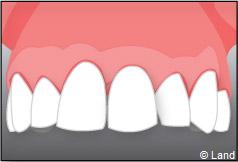

Exemple de 3 dents manquantes remplacées par 3 couronnes sur implants.

Pose des piliers prothétiques et des 3 couronnes scellées.